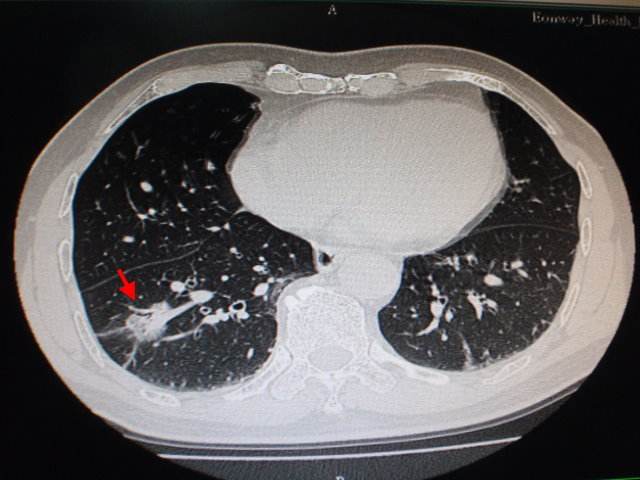

看看她的诊治过程。2018年8,胸部CT提示右肺肿瘤,考虑周围型肺癌,大小约2×2cm,建议手术治疗。手术过程顺利,切除一肺叶。术后病理为肺腺癌,大小约1.5×1.5cm,淋巴结阴性。诊断为:pT1N0M0 Ia期,早期肺癌。同时行基因检测EGFR 19突变。因为是早期肺癌,后续无需特别化疗、放疗等。

胸部CT